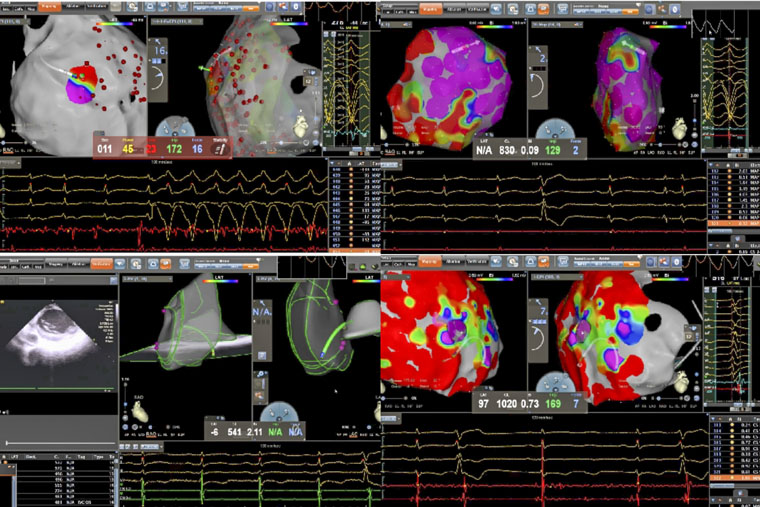

病理性室速通常指由器质性心脏病(如心肌梗死、心肌病等)所导致的室性心动过速。一名患者所患的ARVC,是一种以右心室心肌被纤维脂肪组织替代为特征的遗传性疾病,异常的心肌结构易形成异常电传导通路,从而引发药物难以控制的恶性室速,传统治疗难度大、复发率高。术中,手术团队在X线透视引导下施行心包穿刺,有效规避冠状动脉及心肌损伤风险,为心外膜途径消融建立安全通道。在此基础上,同步进行心内膜及心外膜高密度标测,于右心室多部位识别出低电压区、延迟电位等异常电活动特征,精准判定参与心动过速的关键区域,依托三维电生理标测系统,完成了心内膜与心外膜联合消融。

另一名患者为61岁男性,术前发现频发室性早搏(24小时超过10930次),部分呈三联律及短阵室速,心电图提示起源点为左室乳头肌。频发室早对即将接受大型癌症手术的患者构成多重威胁,如麻醉可能诱发恶性心律失常、室早会影响血流动力学稳定、心脏问题还可能延误肿瘤手术时机。心内科与胃肠外科、麻醉科迅速启动MDT讨论,一致认为必须在肿瘤手术前根除室早这一“定时炸弹”。团队即刻启用“电生理第三只眼”——心腔内超声(ICE)引导手术:ICE导管送入心腔,实时显示左室内乳头肌形态、位置及导管贴靠情况;在ICE引导下克服乳头肌移动难题,实现稳定贴靠与精准消融;ICE实时监测心包情况,极大避免并发症的发生。术后患者室早完全消失,心脏风险解除,并于次日顺利接受贲门癌根治术,现已康复出院。

姚铁柱副主任表示,两例手术的成功实施,共同依托于术前的充分评估与个体化方案设计,先进的影像引导技术(X线、三维标测、ICE)以及手术团队娴熟的技术配合与对心律失常机制的深刻理解。